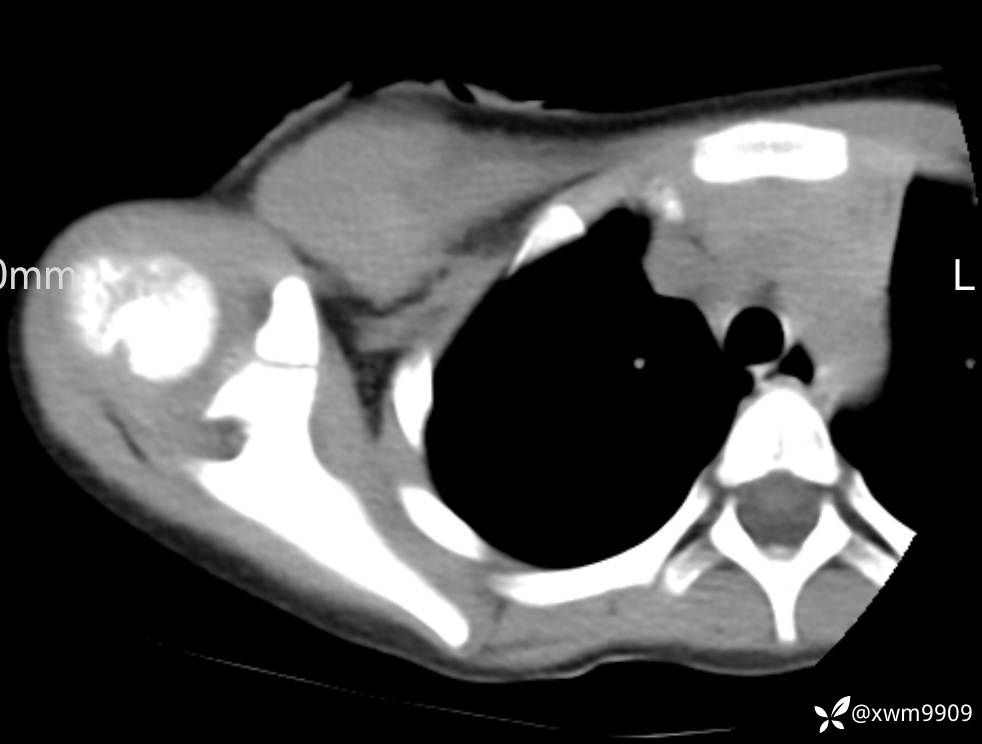

CT:

3、查体,右锁下方可及一约5x6Cm肿物,软丶边清丶未见明显发红,肤温不高,压痛明显,不可推动,稍有波动感。其他无特殊。

2024-03-20,女,6岁。因“发现右侧胸部肿物伴疼痛1天”入院。